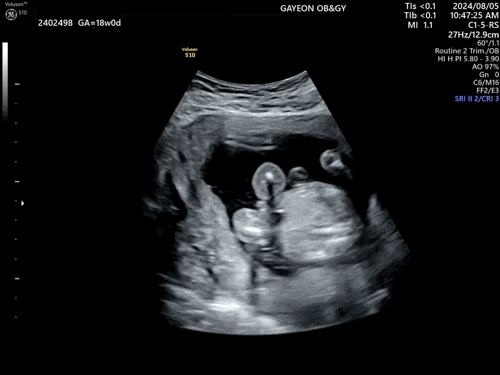

[임신18주] 성별 확인.

24년 8월 5일 드디어 매실이 성별 확인하는 날. (그리고 벌써 임신 18주!) 아들이다(!) 아들일 거 같다(!!)...